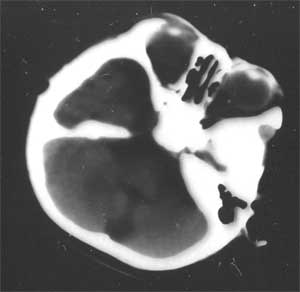

幕上幕下脑室、脑池、脑沟均见扩张积液,考虑脑发育不良。片子质量不好,前囟门似乎偏小,颅骨骨缝不知是否有闭合。9个月幼儿,头围应该不小于40厘米,请测量头围周径。应该没有胼胝体发育不良。至于“右侧基底节区缺血性改变”,片子质量差,看不清楚。

从ct片看1大脑纵裂增宽2侧脑室扩大3蛛网膜下腔增宽 应考虑1胼胝体发育不良,2脑发育不良或萎缩(两周前一般无临床意义应称蛛网膜下腔增宽或外周性脑积水)

胼胝体发育不良可分为全部或部分缺如,常伴发透明隔和穹窿缺如.脑积水及脑小畸形,还可伴发胼胝体脂肪瘤或纵裂蛛网膜囊肿,ct表现为:侧脑室额角和体部间距宽大,而且两侧侧脑室平行分离,枕角呈不对称性扩大(螅室)三脑室轻度扩大并抬高.不同程度地延伸至双侧脑室 中间位置,monro区常拉长.

不同意胼胝体发育不良的诊断,现在ct表现为脑沟、脑池增宽,双测额骨内板下方带状液体影,双测侧脑室略扩大,我认为应诊断为1、脑发育不全。2、外部性脑积水。情况应该很严重。

粗看:1。双侧额颞顶叶均有不同程度萎缩,脑实质变薄,2。脑室系统对称性扩张,大脑沟裂增宽变深。3。双基底节区未见明确低密灶,胼胝体发育良好。综上所述考虑有:1)大脑发育不良;2)严重脑缺血缺氧性脑病后遗症?个人意见仅供参考。

2 患儿有外部性脑积水,但其实质是蛛网膜下腔的增宽,为自愈性,无需处理,一般前囟闭合后便自行消失。ct表现为大脑纵裂和双额颞区蛛网膜下腔增宽,可有轻度的脑室系统扩张。

3 本例 患儿除外部性脑积水外的确有其他部位脑沟的增宽,尤以双顶叶为著,右侧基底节区可见低密度灶,以上可以为新生儿缺氧缺血性脑病所遗留,但并不严重,我想随着治疗锻炼患儿恢复应该会不错的。[em1][em4][em9][em14]